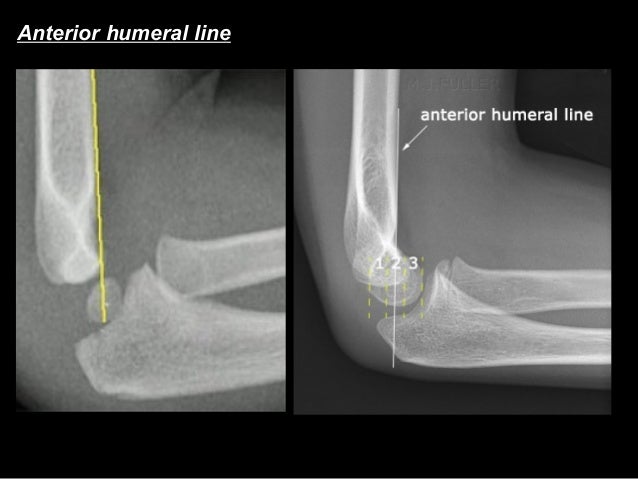

humeral line anterior elbow supracondylar pediatric fractures normal radiology fracture humerus radiopaedia capitellum angle capitulum joint case types injuries occult

elbow ray radial fracture head normal alignment line anterior humeral coreem

elbow forearm normal lateral alignment anterior capitellum radiograph interpreting radiographs fracture supracondylar intersect

elbow line anterior normal radiocapitellar humeral fractures adults lateral radiograph dislocations imaging

humeral radiocapitellar elbow radiographic

elbow humeral fracture supracondylar forearm capitellum radiographs interpreting intersect

elbow xrays humeral radiocapitellar emdocs fracture

elbow xrays anterior humeral radiocapitellar emdocs fracture

radiopaedia line humeral anterior radiology

humeral anterior line pediatric fracture abnormal pedia

capitellum dislocation elbow pediatric through drawn lateral anterior humeral pass should line

Anterior humeral line. Pediatric humeral fracture. Elbow injuries